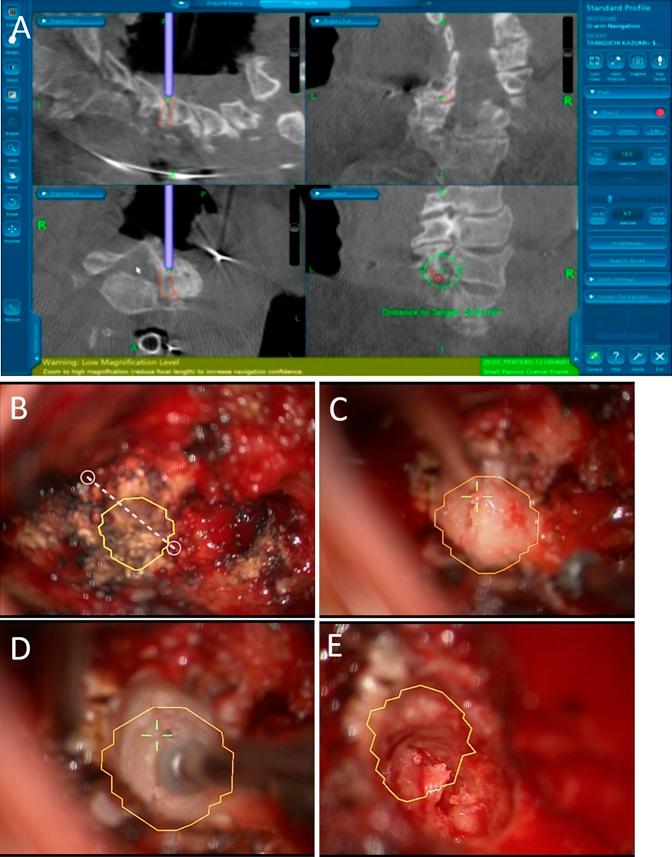

增强现实可视化引导下的显微镜脊柱手术:经椎间隙前路颈椎椎间孔切开术和后路椎间孔切开术。

Augmented Reality Visualization-guided Microscopic Spine Surgery: Transvertebral Anterior Cervical Foraminotomy and Posterior Foraminotomy.

We describe intraoperative augmented reality (AR) imaging to obtain a microscopic view in spine keyhole surgery.

Minimally invasive keyhole surgery has been developed even for spine surgery, including transvertebral anterior cervical foraminotomy and posterior cervical laminoforaminotomy. These methods are complex and require a skillful technique. Therefore, inexperienced surgeons hesitate to perform keyhole surgeries. The technology used in surgery is rapidly advancing, including intraoperative imaging devices that have enabled AR imaging and facilitated complicated surgeries in many fields. However, data are not currently available on the use of AR imaging in spine surgery. The purpose of this article was to introduce the utility of AR for spine surgery.

We performed O-arm intraoperative imaging to create an augmented imaging model in navigation systems. Navigation data were linked to a microscope to merge the live view and AR. Augmented reality imaging shows the model plan in the real-world surgical field. We used this novel method in patients who underwent both keyhole surgeries.

We successfully performed both surgeries using the AR visualization guide.

The AR navigation system facilitates complicated keyhole surgeries in patients who undergo spine surgery.

我们描述了术中增强现实(AR)成像技术,以在脊柱锁孔手术中获得微观视野。

即使是脊柱手术,包括经椎体前路颈椎椎间孔切开术和后路颈椎椎板间孔切开术,也已发展出微创锁孔手术。这些方法操作复杂,需要熟练的技术。因此,经验不足的外科医生对进行锁孔手术犹豫不决。手术中使用的技术正在迅速发展,包括术中成像设备,这些设备已实现AR成像,并在许多领域促进了复杂手术的开展。然而,目前尚无关于AR成像在脊柱手术中应用的数据。本文的目的是介绍AR在脊柱手术中的实用性。

我们进行了O型臂术中成像,以在导航系统中创建增强成像模型。将导航数据与显微镜相连,以融合实时视野和AR。增强现实成像在真实的手术视野中显示模型规划。我们在接受两种锁孔手术的患者中使用了这种新方法。

我们使用AR可视化引导成功完成了两种手术。

AR导航系统有助于为接受脊柱手术的患者进行复杂的锁孔手术。